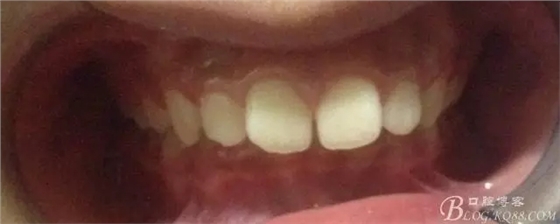

術前側貌,下合后縮還算明顯,正面照有點看不出的樣子!